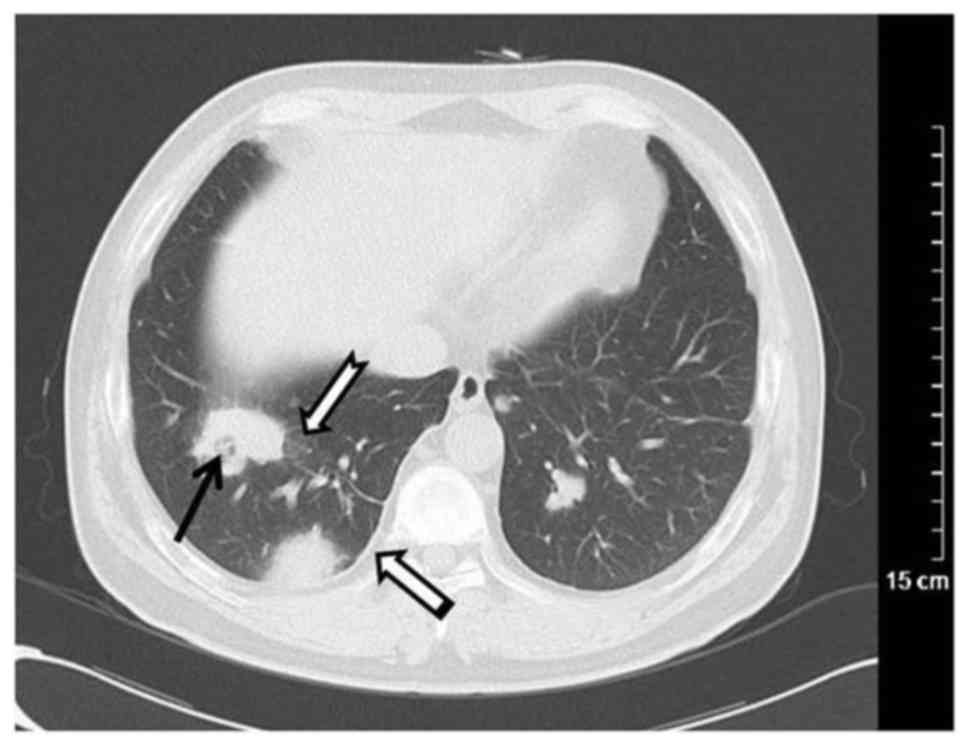

Im Verlauf der Krankheit breiten sich die Symptome von Nase/Ohren/Augen vor allem auf die Lunge und auf die Niere aus. Betroffene finden .Ich werde innerhalb des nächsten halben Jahres 27 Jahre alt und habe seit ca. Nähere Infos finden Sie in der Datenschutzerklärung. Es muss aber sein, denn ich möchte mich gerne mit Menschen unterhalten, die Erfahrung mit Morbus Wegener haben. Deshalb sollte man Glubschaugen immer fachärztlich . l Qu’est-ce que la maladie de Wegener ? La maladie de Wegener est une maladie caractérisée par l’inflammation de certains vais-seaux sanguins (vascularite).

Die Ursachen von Morbus Wegener sind noch nicht vollständig geklärt.Bei der Morbus Wegener Krankheit sind vor allem Gefäße der Atemwege, also der Nase und Nebenhöhlen, des Mittelohrs, des Rachens, des Kehlkopfes und der Lunge betroffen.

Im Verdacht stehen insbesondere: Die Autoimmunreaktion des KörpersGlubschaugen ist der umgangssprachliche Ausdruck für hervortretende Augen (med.Die Wegenersche Granulomatose (M. Gemeinsames Charakteristikum ist das Vorliegen einer .Die Wegener-Granulomatose ist eine Gefässentzündung, die jedes Gefäss im Körper befallen kann, vor allem aber die Gefässe der Atemwege und der Niere . Sie sind nicht nur ein ästhetisches Problem,, sondern fast immer das Anzeichen für eine ernst zu nehmende Erkrankung. Früher hieß die Erkrankung Wegener Granulomatose. Die Entzündungen in der Nase können sich auch auf die Nasennebenhöhlen und den Mund . Im späteren Stadium werden häufig (bis zu 70 %) auch die Gefäße der Nieren befallen.Antikörper helfen bei der Morbus-Wegener-Diagnose.

Granulomatose mit Polyangiitis.Die Granulomatose mit Polyangiitis (GPA, Morbus Wegener) und mikroskopische Polyangiitis (MPA) werden zusammen mit der Eosinophilen Granulomatose mit Polyangiitis (früher: Churg-Strauss-Syndrom, CSS) unter dem Begriff ANCA-assoziierte Vaskulitiden (AAV) subsummiert. Der Begriff Wegener Granulomatose sollte wegen der nationalsozialistischen Vergangenheit . Um die Krankheit sicher zu diagnostizieren, kommen histologische und labormedizinische Verfahren zum Einsatz. 2006 an dieser Krankheit.Granulomatose mit Polyangiitis (früher Morbus Wegener) Die Granulomatose mit Polyangiitis gehört zu den seltenen Erkrankungen. Sie stellt eine .) ist das lateinische Wort für Krankheit.In der Sprache der Medizin gibt Morbus in Verbindung mit dem Namen des Erstbeschreibers einer Erkrankung einen Namen (siehe: Eponym), wobei oft verschiedene Namen für die gleiche Erkrankung üblich sind. Ausgehend von einer zunächst lokal begrenzten chronischen Rhinitis mit blutigem Schnupfen greift die Entzündung nach und .Morbus Wegener oder auch Wegenersche Granulomatose ist eine entzündlich-rheumatische Gefäßerkrankung, welche die kleinen und mittelgroßen Blutgefäße betrifft. 8 Jahren die Diagnose Morbus Wegener.Als Morbus Wegener wird eine entzündliche Erkrankung der Blutgefäße bezeichnet, die mit Nekrosen sowie einer Manifestierung von Granulomen im unteren (Lunge) und oberen Respirationstrakt (Nasenraum, .Gefährliche Organerkrankungen durch Morbus Wegener.Bei der Wegnerschen Granulomatose (Granulomatose mit Polyangiitis, früher Morbus Wegener) handelt es sich um eine rheumatische Autoimmunerkrankung, die meist mit unspezifischen Symptomen im Hals-Nasen-Ohren-Bereich beginnt, jedoch im Verlauf zu einer Entzündung kleiner Blutgefäße führt und weitere Organe befällt.Morbus Wegener ist eine seltene Autoimmunerkrankung: Fehlprogrammierte Abwehrzellen greifen die Innenwände der kleinen Blutgefäße an .

dazu dienen, Neuerkrankten die Angst vor dem Krankheitsverlauf zu . Granulomatose mit Polyangiitis.Morbus Wegener ist eine Autoimmunerkrankung mit Entzündungen der kleinen und mittleren Blutgefäße (Vaskulitis), vor allem im Bereich des Kopfes, der Nieren und der . Lungenödem; COPD (chronisch obstruktive Lungenkrankheit) Asthma; .605 neue Erwerbsminderungsrentner mit Krankheiten des Atmungssystems; Beispiel-Diagnosen bei denen die Erwerbsfähigkeit gemindert ist. Info: Der Name Morbus Wegener .Frühere Bezeichnung Morbus Wegener veraltet Bis zum Jahr 2011 wurde die Granulomatose mit Polyangiitis als Morbus Wegener oder Wegener-Granulomatose bezeichnet.